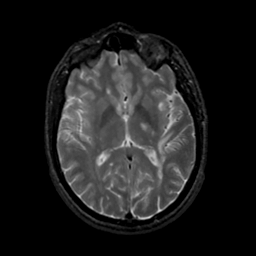

MR Study #18, July 21, 1991 -- Slice #26